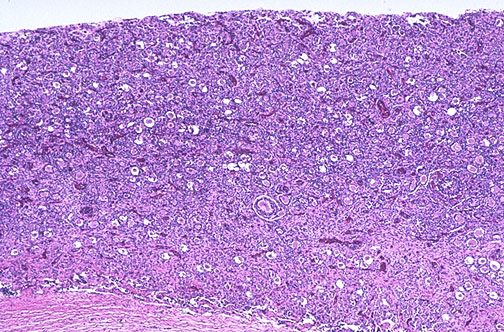

Normal fetal ovary at low magnification reveals numerous primordial follicles and little intervening stroma. Near the center a follicle shows enlargement under the influence of maternal hormones in utero.